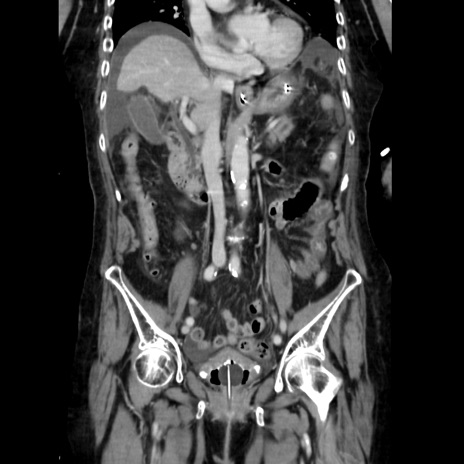

症例40(冠状断像)

【症例】90歳代女性

【主訴】腹痛・嘔吐

【現病歴】 食欲低下、嘔吐があり昨日他院受診。肺炎と診断され入院となる。入院後より腹部全体に圧痛あり。胃管留置され経過みていたが、症状持続するため、

当院転院となる。

【既往歴】胸椎圧迫骨折、胆石症

【身体所見】腹部:中央に激痛あり、圧痛あり、反跳痛不明

【データ】WBC 17100、CRP 18.82

冠状断像